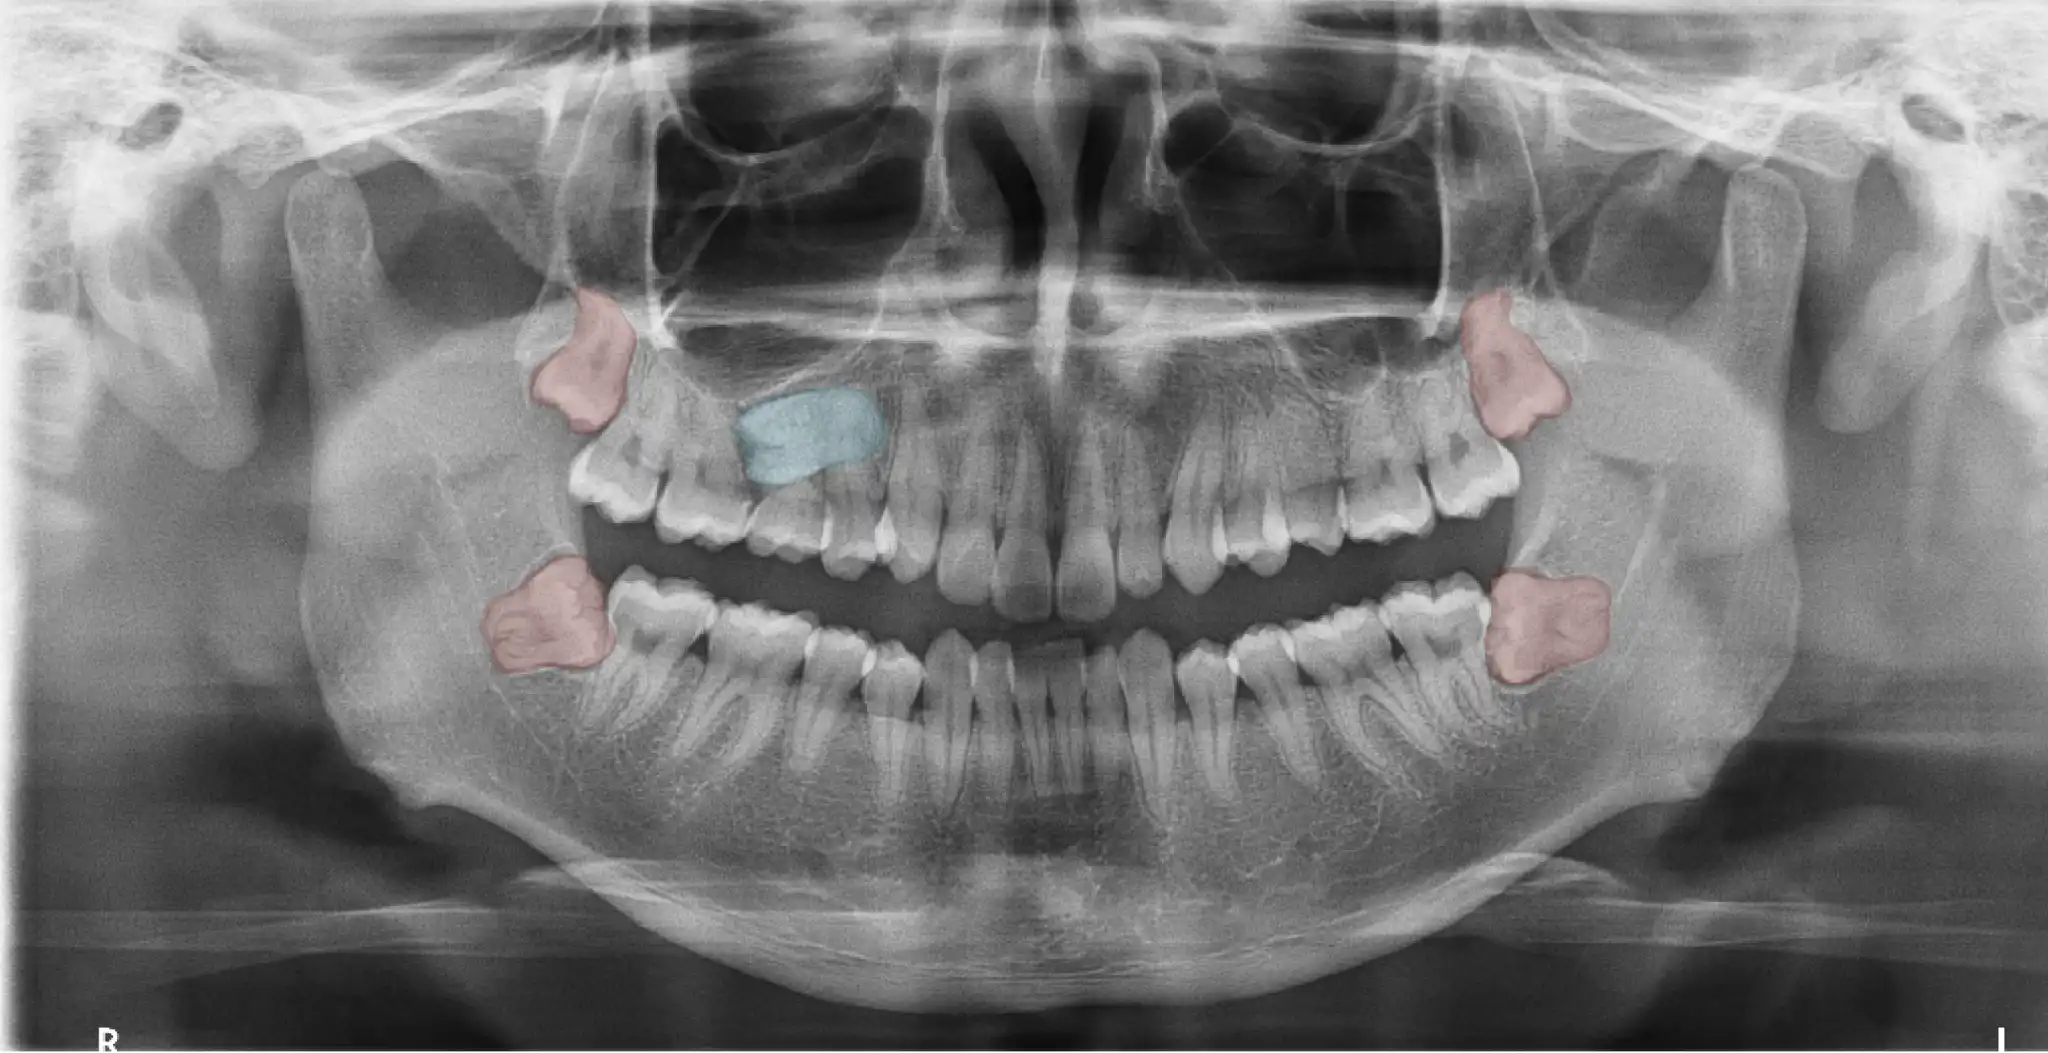

Difficult vertical Impacted wisdom teeth case. Distal impaction of Tooth 38 (lower left)with curve mesial root hiding behind Tooth 37, root tip is close to nerve. Extraction for resolving wisdom teeth gum infection and improving orthodontic treatment retention.

Unerupted wisdom teeth 18 (right upper) and 28 (left upper). Tooth 48 (lower right) with very curved root and is close to nerve. Tooth 38 (bottom left) horizontal impacted with two strong wide open curve roots close to nerve.